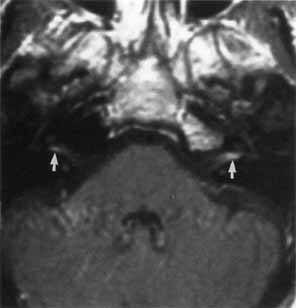

hemifacial spasm with magnetic resonance imaging: Comparison with surgical

findings in 60 consecutive cases. Surg Neurol 59(2):93, 2003 132. Jannetta PT, Abbasy M, Marion JC: Etiology and definitive microsurgical treatment of hemifacial spasm: Operative

techniques and results in 47 patients. J Neurosurg 47:321, 1977 133. Gardner WJ, Sava GA: Hemifacial spasm: A reversible pathophysiologic state. J Neurosurg 19:240, 1962 134. Nielsen VK: Pathophysiology of hemifacial spasm: A reversible pathophysiologic state. Neurology 34:418, 1984 135. Ferguson JH: Hemifacial spasm and the facial nucleus. Ann Neurol 4:97, 1978 136. Davis WE, Luterman BF, Pulliam MW: Hemifacial spasm caused by cholesteatoma: Am J Otol 2:272, 1981 137. Adler CH, Zimmerman RA, Savino PJ: Hemifacial spasm: Evaluation by magnetic resonance imaging and magnetic

resonance tomographic angiography. Ann Neurol 32:502, 1992 138. Auger R, Piepras D, Laws E: Hemifacial spasm: Results in microvascular decompressions of the facial

nerve in 54 patients. Mayo Clin Proc 61:650, 1986 139. Huang CI, Chen IH, Lee LS: Microvascular decompression of hemifacial spasm: Analysis of operative

findings and results in 310 patients. Neurosurgery 30:53, 1992 140. Garland PE, Patrinely JR, Andreson RI: Hemifacial spasm: Results of unilateral myectomy. Ophthalmology 94:288, 1987 141. Alexander GE, Moses H: Carbamazepine for hemifacial spasm. Neurology 32:286, 1982 142. Sandyk R: Facial myokymia. J Neurosurg 59:1108, 1983 143. Frueh BR: Associated facial contracting after seventh nerve palsy mimicking jaw-winking. Ophthalmology 90:1105, 1983 144. Lubkin V: The inverse Marcus Gunn phenomenon. Arch Neurol 35:249, 1978 145. Chorobski J: Syndrome of crocodile tears. Arch Neurol Psychiatry 65:299, 1951 146. Axelsson A, Laage-Hellman JE: The gustolachrymal reflex: The syndrome of crocodile tears. Acta Otolaryngol 54:239, 1962 147. Frey L: Syndrome of auriculotemporal nerve. Rev Neurol 2:97, 1923 148. Laage-Hellman JE: Gustatory sweating and flushing. Aetiological implications of latent period